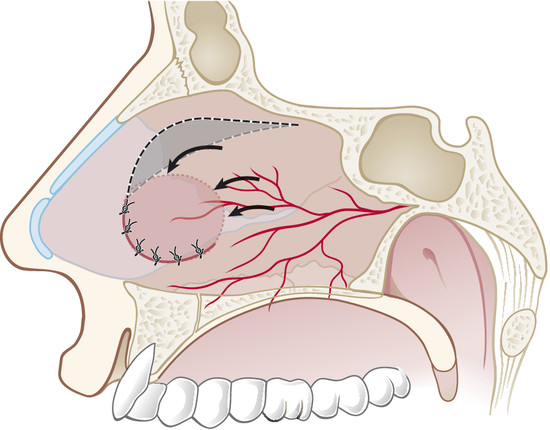

In the case of rounded perforations, a rotation/advancement mucoperiosteal flap is designed by a rounded incision based posteriorly on the nasal-septal artery and elevated up to 1 cm from the choana (Fig. 19‑4). Also, in this case the flap is rotated to reach the inferior border of the perforation and sutured with a 3–0 Vicryl suture (Fig. 19‑5).